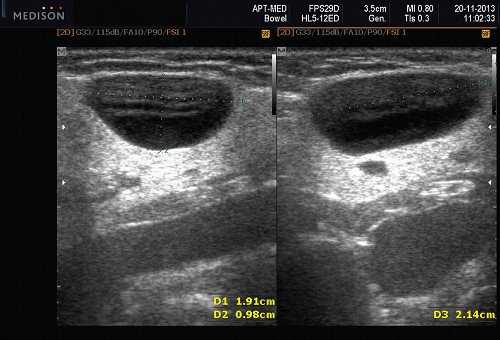

Данные УЗИ слюнных желез при карциноме

- Увеличенное солидное образование околоушной при ультразвуковом сканировании (примерно 75%) или поднижнечелюстной железы (примерно 25%)

- Особенности визуализации неспецифические

- Нечеткие или четко определенные границы.

- Гипоэхогенная, гомогенная или гетерогенная эхоструктура на УЗИ

- Отмечается внутренняя васкуляризация на цветном доплеровском исследовании.

- Могут наблюдаться аномальные интрапаротидные, перипаротидные, шейные лимфатические узлы.

Общие характеристики при ультразвуковом сканировании

- Лучший диагностический признак на УЗИ слюнной железы - Увеличенное солидное образование околоушной или поднижнечелюстной железы

- Место расположения. Околоушная железа: около 75%. Поднижнечелюстная железа: около 25%. Другие места в голове и шее (редко) - дно полости рта, язык, миндалины, мягкое небо, гортань, гортань. Остальная часть тела (редко) - легкие, тимус, желудок и двенадцатиперстная кишка, грудь, почечная лоханка и мочевой пузырь, шейка матки, эндометрий, яичник, влагалище

- Размер 1-5 см.

- Морфология переменная. Четко очерченные, дольчатые до инфильтративного типа края

Результаты ультразвукового исследования слюнной железы

- Серошкальное УЗИ. Одиночное солидное образование в паренхиме околоушной или подчелюстной железы. Может иметь хорошо выраженные, дольчатые или плохо очерченные / инфильтративные границы. Гипоэхогенная структура по отношению к паренхиме слюнной железы. Общее улучшение ультразвукового изображения задних структур. Иногда центральный кистозный компонент представляет некроз. Могут наблюдаться связанные аномальные интрапаротидные, перипаротидные, шейные лимфатические узлы

- Цветной допплер. Внутриузловая васкуляризация от умеренной до выраженной